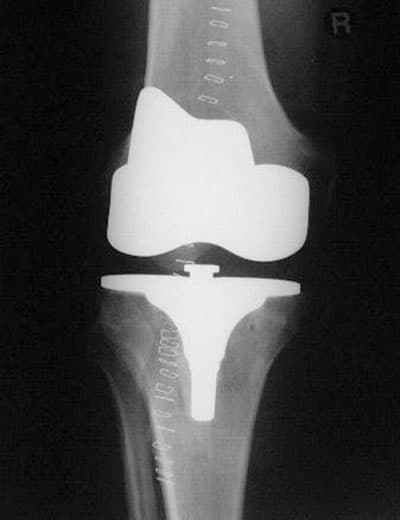

تستبدل المفاصل الطبيعية عند تلف وزوال المادة الغضروفية في المفصل نتيجة التهاب المفصل العظمي أو أحد أنواع التهابات العظم الروماتيزمية، وأكثر الأنواع شيوعاً هو "الاحتكاك، ويعد المفصل الصناعي الطريق الأمثل لتحسين الحركة للتخلص من الآلام واستعادة استقلالية القدم، وجراحة استبدال المفصل الصناعي أكثر الطرق فعالية للتخلص من الآلام المبرحة في المفصل، ويتم ذلك بواسطة استبدال الأسطح التالفة، وأيضاً عن طريق تعديل استقامة القدم وتحسين آلية الركبة، ما يسمح للعضلات التي أضعفها الاحتكاك على استعادة قوتها، وجراحة استبدال المفصل هي خصوصاً للمرضى الكبار السن.

وفي بعض الأحيان لمتوسطي العمر وأن زراعة المفاصل من أكثر العمليات التي أثبتت نجاحها في الوقت الذي زادت فيه الخبرات بشكل كبير، وهنا يأتي دور العمل الجراحي، حيث يتم تغطية السطوح المفصلية المتعرية بقطع معدنية وبلاستيكية تشابه في شكلها المفصل الطبيعي، وبهذا تخف معاناة المريض من الألم ويستعيد المفصل قدرته على الحركة بشكل شبه تام يسمح للمريض بأداء الكثير من النشاطات اليومية في حياته.

إن عمليات المفاصل من العمليات الشائعة في الغرب وأكثرها في مفصل الورك والركبة والكتف والكوع والفائدة الرئيسة للمفصل الصناعي هي تناقص الألم المستمر، ويشعر أن الطرف أصبح أقوى من قبل، وأن الحركة غير مؤلمة، كما يلاحظ كثير من المرضى تحسنا في حركة المفصل، ففي حالة مفصل الكتف الصناعي يلاحظ المريض أنه يستطيع بعد العمل الجراحي تسريح شعر رأسه والنظافة الشخصية وتغيير ملابسه دون مساعدة ويستطيع رفع الأشياء بشكل أفضل، أما في حالة مفصل الورك والركبة فإن المريض يستطيع المشي دون ألم لمسافات طويلة وحركة المفصل تصبح أفضل ودون ألم كذلك فإن شكل الساق يصبح أفضل، حيث يكون قبل العملية مقوسا ويصبح بعد العمل الجراحي مستقيما وذا منظر طبيعي.

لقد أثبتت المفاصل الصناعية نجاحها، فقد تطورت تطوراً سريعاً خلال السنوات العشر الماضية ولقد بدأ استخدامها منذ 30 عاماً، ونظراً لما يعترض مفصل الركبة من إصابات تؤدي إلى تلفه فقد حصلت تطورات كثيرة على المفصل الصناعي للركبة خلال السنوات الخمس الماضية، والمفصل الصناعي للركبة يلائم صغار السن وأكثر ثباتاً. وإن أكثر مضاعفات جراحة الركبة هي الالتهابات، حيث تبلغ نسبة هذه المضاعفات 1 في المائة فقط في المراكز الطبية المتميزة، وهي نسبة ضئيلة ولكنها إن حدثت فهي مشكلة كبيرة، عندها قد نضطر إلى نزع المفصل الصناعي ونضع مكانه مضاداً حيوياً على شكل طبقة طبية، وقد يخضع المريض لفترة من العلاج قبل وضع المفصل الصناعي من جديد، كما تشمل بعض المضاعفات الأخرى كجلطات الدم في القدم التي من الممكن السيطرة عليها بشكل فاعل بالتحرك المبكر وباستخدام الأسبرين ومسيلات الدم الأخرى، وجعل المريض يتحرك مبكراً لمنع حدوث الاحتقان في الرئتين.

ومفصل الركبة من المفاصل المهمة التي تقوم بدور عظيم في حياة الإنسان، فعليها يتم حمل الجسم "إضافة إلى المفاصل الأخرى في الأطراف السفلية"، وهو مفصل دقيق ومعقد، وما يميزه من الناحية التشريحية عدم وجود طبقة عضلية سميكة تغطيه، وهذا ما يجعل عملية إجراء المفاصل الصناعية من الناحية العملية أمراً ليس بالهين، ويحتاج إلى الكثير من الخبرة والدقة لإجرائه، فهناك الكثير من النقاط التي يجب مراعاتها أثناء العمل الجراحي إلا أن التطورات الأخيرة في مجال المفاصل الصناعية ووجود نخبة من الجراحين وازدياد الخبرات في ذلك جعل نتائج العمليات أفضل بكثير من ذي قبل، وأصبح بإمكان الكثير من المرضى ممارسة حياتهم بشكل قريب جداً إلى المستوى الطبيعي، وعلى المريض أن يستشير طبيبه كي يساعده على اتخاذ القرار واللجوء إلى الحل الجراحي.